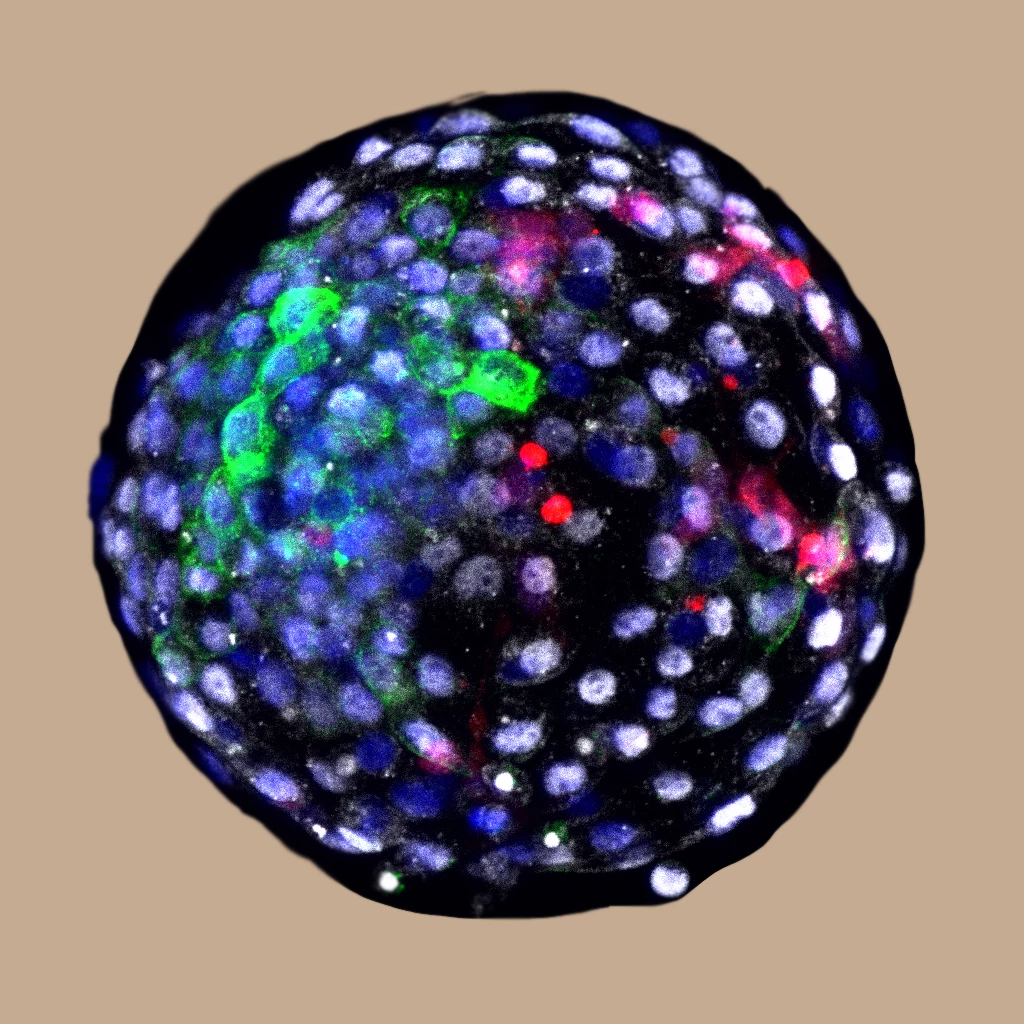

In lab tests in culture, the team started with monkey blastocysts. Six days after fertilization they were injected with 25 human extended pluripotent stem (hEPS) cells, which contribute to the tissue as the embryo develops.

And sure enough, when the researchers examined the batch of embryos 24 hours later, they detected human cells in 132 of them. After 10 days, there were 103 of these chimeric embryos remaining, but by day 19 only three still survived. After that, the embryos were terminated before they developed any further.